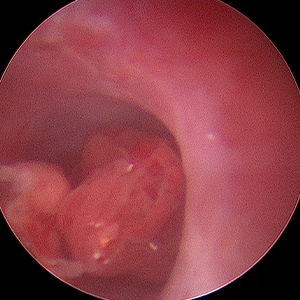

비강 내시경

비강 내시경은 만성 비출혈, 재발성 재채기, 이물, 또는 종양 등 다양한 비강 증상의 원인을 파악하고, 조직검사·이물 제거가 가능합니다.

비강 종양 예시 이미지

비강종양